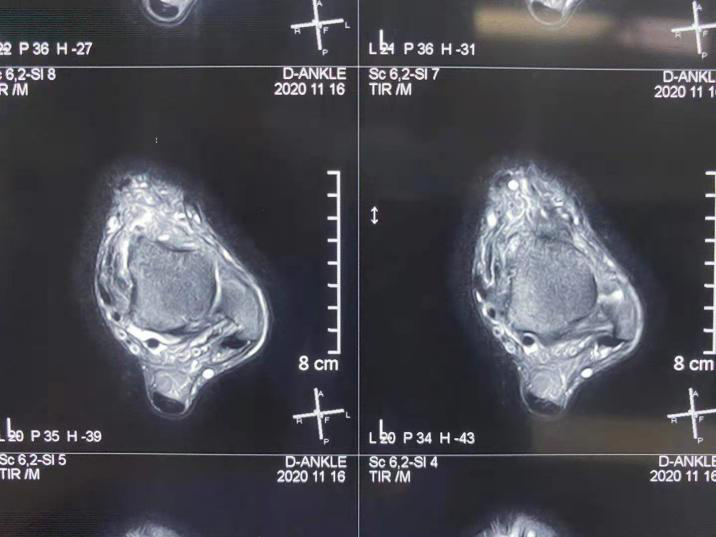

近期,我院骨科四病区刘京升主任团队积极进行学科内交叉合作,在踝关节扭伤导致的慢性踝关节不稳诊治方面积累了丰富经验,进一步推动了省内足踝外科的发展。

科室副主任医师王凯查阅大量文献,总结既往踝关节反复扭伤的典型病例特点,并对多例病例进行随访,发现人工韧带结构在治疗慢性踝关节不稳的中远期效果与传统踝关节外侧副韧带重建手术效果相当,但是手术步骤及手术时间大大缩减,术后并发症明显减少,同时患者生活质量明显提高。

目前,骨科四病区通过人工韧带结构治疗慢性踝关节不稳,遵循等长收缩的原理,更符合踝关节生物力学的特点,术后不限制后足的活动,既没有破坏受损踝关节周围的正常组织,而且由于人工韧带结构强度高,又能有效的保证术后踝关节的稳定性,远期效果显著。此手术方式可有效地改善患者踝关节的功能,减轻其术后疼痛的程度,促进患者康复,值得后期推广应用。